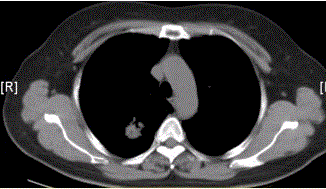

问题 患者女,54岁,无症状,常规体检透视时发现右上肺阴影。既往无结核病史。体格检查阴性。CT结果如下图。 局限性阻塞性肺气肿最常见的病因是

选项 A.支气管哮喘 B.支气管扩张 C.慢性支气管炎 D.大叶性肺炎 E.支气管肺癌 F.支气管囊肿

答案 E